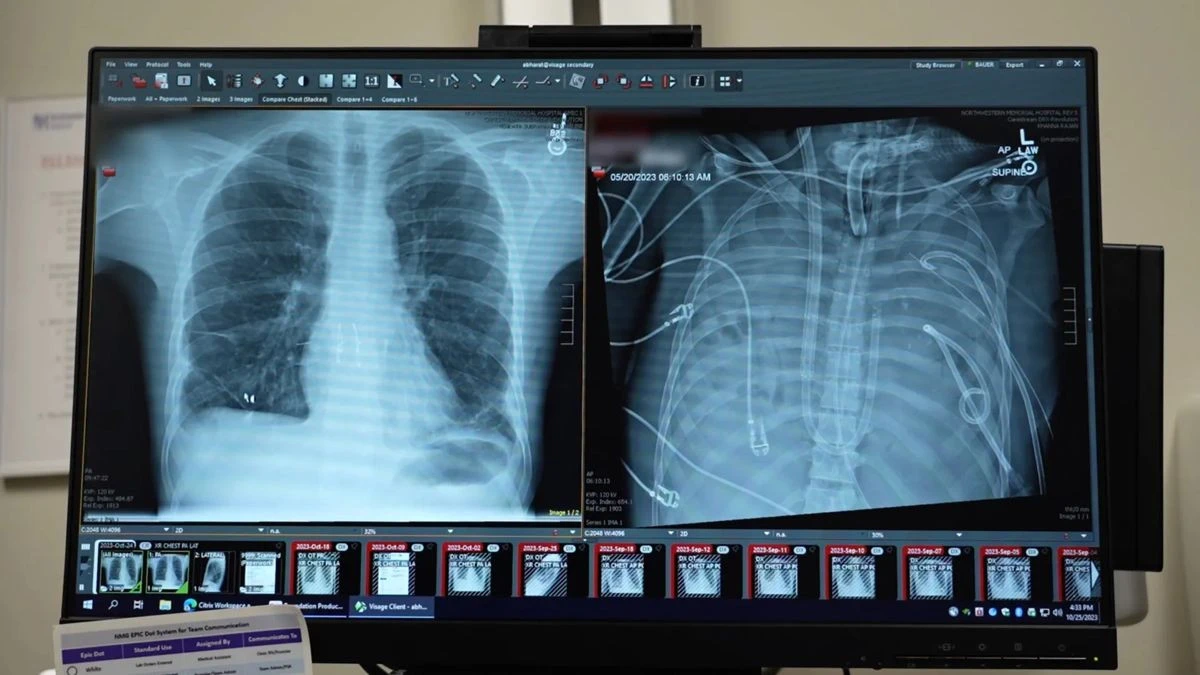

Χειρουργοί στο Northwestern Medicine των Ηνωμένων Πολιτειών κατάφεραν να διατηρήσουν στη ζωή έναν 33χρονο ασθενή για 48 ώρες χωρίς φυσικούς πνεύμονες, χρησιμοποιώντας ένα ειδικά σχεδιασμένο σύστημα εξωσωματικού τεχνητού πνεύμονα (Total Artificial Lung - TAL). Η συγκεκριμένη ιατρική προσέγγιση επέτρεψε την αφαίρεση των μολυσμένων οργάνων, την υποχώρηση της σήψης και τη σταθεροποίηση του οργανισμού μέχρι να βρεθεί συμβατός δότης για διπλή μεταμόσχευση.

Η ιατρική ομάδα υπό τον θωρακοχειρουργό Dr. Ankit Bharat στο Northwestern University βρέθηκε αντιμέτωπη με μια κρίσιμη κατάσταση. Ο 33χρονος ασθενής νοσηλευόταν με σοβαρό Σύνδρομο Οξείας Αναπνευστικής Δυσχέρειας (ARDS), το οποίο προκλήθηκε αρχικά από τον ιό της γρίπης τύπου Β και επιδεινώθηκε ραγδαία λόγω δευτερογενούς βακτηριακής πνευμονίας ανθεκτικής στα αντιβιοτικά. Τα βακτήρια πέρασαν στην κυκλοφορία του αίματος, προκαλώντας πολυοργανική ανεπάρκεια και σηπτικό σοκ.

Οι μοριακές εξετάσεις στους ιστούς, μέσω της μεθόδου RNA sequencing σε επίπεδο μονοκυττάρου, απέδειξαν αργότερα ότι η δομή των πνευμόνων είχε υποστεί ολοκληρωτική και μη αναστρέψιμη καταστροφή. Η παραμονή των νεκρωμένων οργάνων στο σώμα του ασθενούς λειτουργούσε ως συνεχής πηγή μόλυνσης. Η μόνη ιατρική επιλογή ήταν η πλήρης αφαίρεση των πνευμόνων (αμφοτερόπλευρη πνευμονεκτομή) για τον έλεγχο της σήψης, προκειμένου να καταστεί δυνατή η μεταμόσχευση.